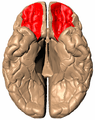

Orbital gyrus shown in red.

Orbital gyrus shown in red. Medial surface of cerebral cortex - gyri

Medial surface of cerebral cortex - gyri Basal surface of cerebrum. Orbital gyrus shown in red.

Basal surface of cerebrum. Orbital gyrus shown in red.